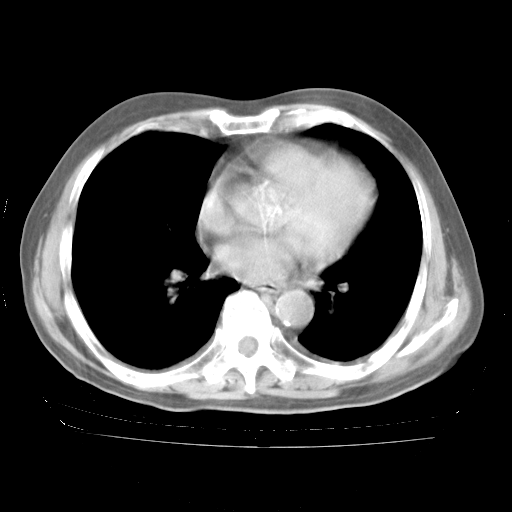

4月28日肺部CT——再次出现类似去年5月9日——透光度降低,“间质性”改变。

4月28日肺部CT——再次出现类似去年5月9日——磨玻璃样、间有“粟粒样”改变。

4月28日肺部CT